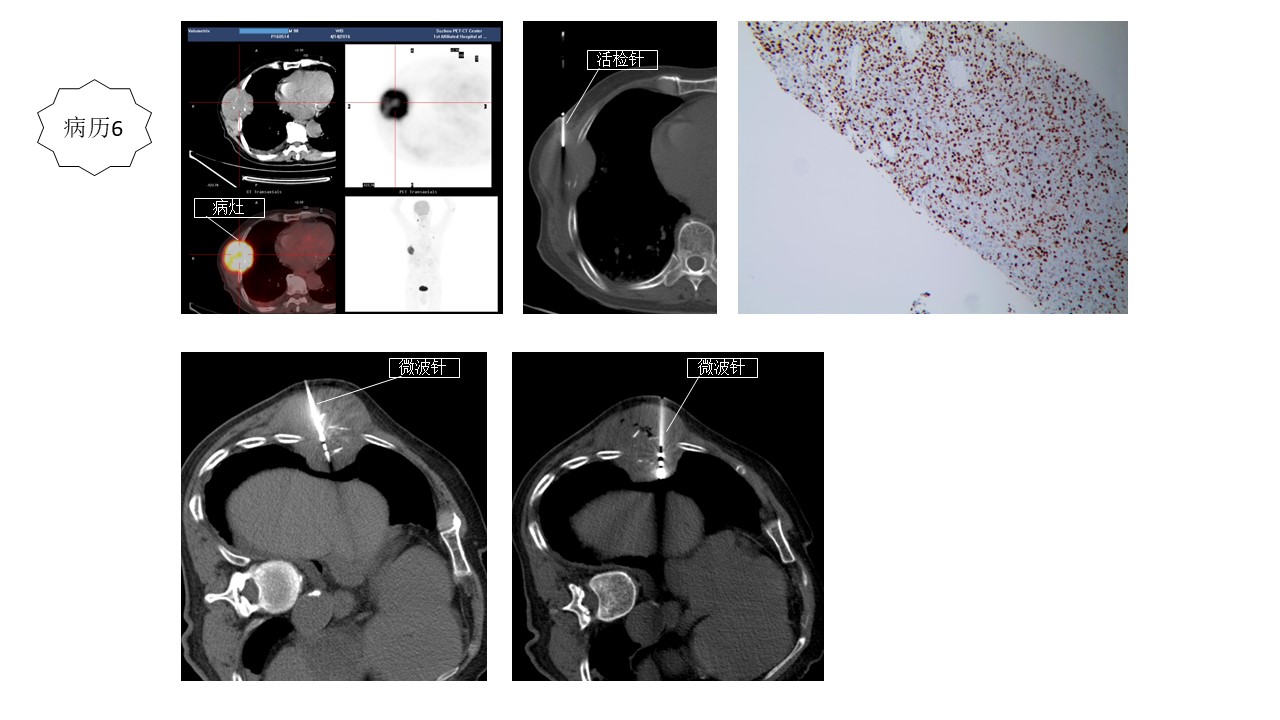

病历6。男,90岁,PET/CT提示右胸壁肿块,伴多处淋巴结肿大,疼痛难忍。穿刺活检,病理为恶性间叶源性肿瘤。行微波消融后,疼痛缓解,肿块张力减轻,缩小。此为姑息性治疗,以改善症状为主。